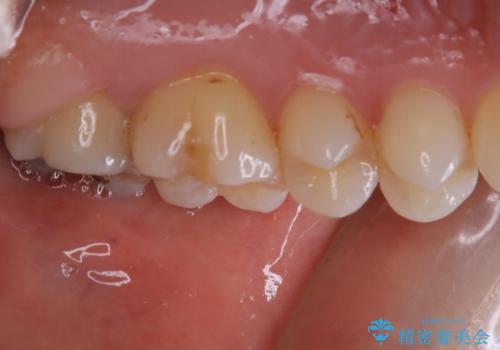

- 一番奥の歯に違和感がありご来院頂いた患者様です。

診断の結果、一番奥の歯は失活していたため精密根管治療から治療介入となりました。奥から2番目の歯にも大きな虫歯が認められたため、セラミックインレーによる補綴治療を行いました。 精密根管治療は患者様のご希望により、福本院長に行っていただきました。